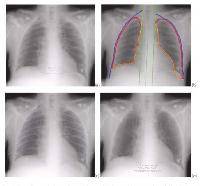

Изучение проблемы низкого качества рентгенограмм на Вашем оборудовании.